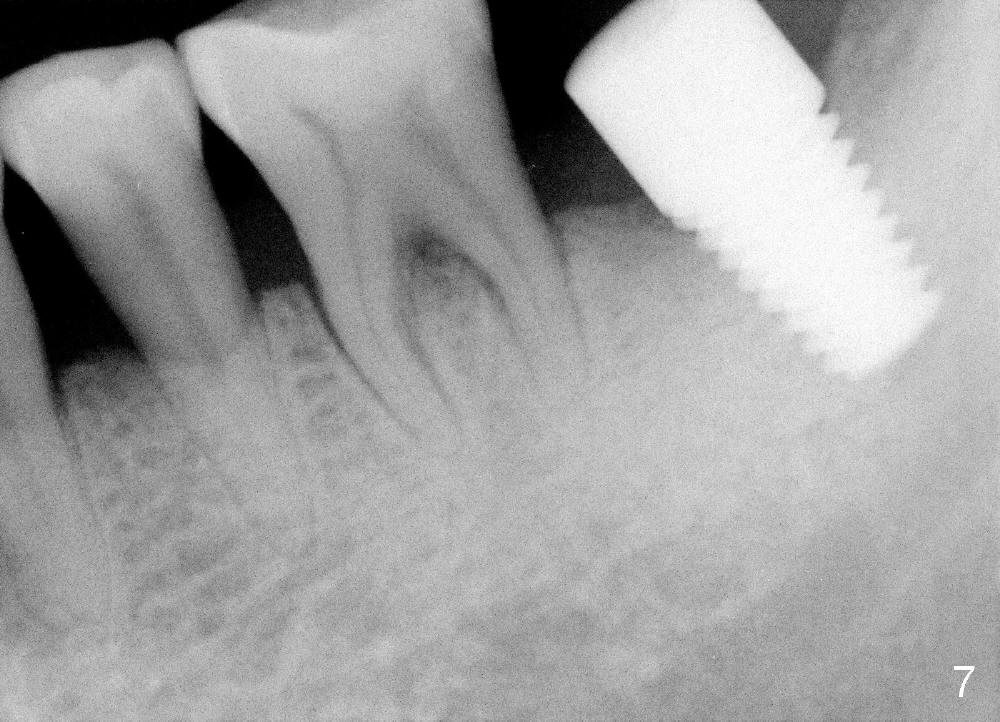

In contrast, the patient is asymptomatic after the 2nd placement. The implant remains stable (Fig.6 (15 days postop); Fig.7 (4 months postop)).

There is no bone resorption 6 months post cementation (12 months postop, Fig.8,9). Mild bone resorption is observed 3 years post cementation (Fig.10). It may be related to the large implant (7 mm) in association with chronic periodontitis and bruxism. The roots of the teeth #19 and 30 fracture 6 years 5 months post cementation at #18 (Fig.11). Since gingival recession is severe at #18 probably related to the large implant, the one at #19 will be designed small.